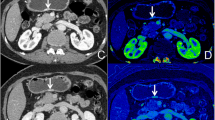

Initially, conventional polychromatic images were used to identify the volume of interest (VOI) for the whole tumor. All lesions had regions of interest (ROIs) drawn slice-by-slice on the 2D images, with the contour drawn slightly within the margins of the tumor masses to avoid including adjacent air or fat. The corresponding sagittal and coronal planes of the tumors might be utilized as a reference if the lesion was difficult to recognize in the axial plane. The ROIs were then used to reconstruct VOIs. The resulting 3D segmentation was then replicated onto the geometrically identical images of the IMD images. Figure 2 depicts a manual segmentation example in action.